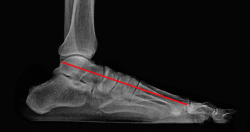

Para ello, se han estudiado radiografías de ambas entidades clínicas. Mediante la línea de Meary(3), que en un pie normal es rectilínea y atraviesa el talus, el navicular y el primer metatarsiano, se ha buscado el punto de rotura o inflexión de dicha línea en pies planos y pies cavos (Figura 1).

Figura 1. Radiografía de perfil en carga. La línea de Meary atraviesa el talus, el navicular, el cuneiforme medial y el primer metatarsiano.